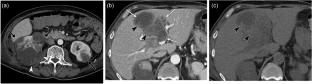

我们报告一例60多岁的ROS1融合阳性肺腺癌患者在克唑替尼治疗期间肾脏和肝脏出现多发性囊性病变。患者表现为发热、腹痛和少尿。增强CT显示肾脏和肝脏出现新的囊性病变,部分显示壁厚、间隔和高密度内容物。MRI显示t2加权图像信号强度不均,t1加权图像信号强度高低混合。部分囊肿沿囊肿壁呈T2低信号区和T1高信号区,扩散限制主要在肿块周围。经皮对囊肿进行引流,细胞学检查显示细胞数量增加,包括中性粒细胞。但未检出恶性细胞或微生物。基于这些影像学表现和实验室结果,患者被诊断为与克唑替尼相关的肾和肝囊肿。停用克唑替尼后症状改善,随访影像显示囊肿消退。这是第一份描述克里唑替尼相关肝囊肿MRI表现的报告。特征性MRI表现,如沿囊肿壁T2低/T1高,扩散限制主要在肿块周围,提示出血性成分,可能有助于区分克唑替尼相关囊肿与其他病变,包括转移和脓肿。

We report a case of a man in his 60s with ROS1 fusion-positive lung adenocarcinoma who developed multiple cystic lesions in both the kidneys and liver during crizotinib treatment. The patient presented with fever, abdominal pain, and oliguria. Contrast-enhanced CT revealed new cystic lesions in both the kidneys and liver, with some showing thick walls, septa, and hyperdense contents. MRI demonstrated heterogeneous signal intensities on T2-weighted images and mixed low to high signal intensities on T1-weighted images. Some cysts displayed T2 hypointense and T1 hyperintense areas along the cyst walls, with diffusion restriction predominantly at the periphery of the masses. Percutaneous drainage of the cysts was performed, and cytology revealed an increase in the number of cells, including neutrophils. However, no malignant cells or microorganisms were detected. Based on these imaging findings and laboratory results, the patient was diagnosed with crizotinib-associated renal and hepatic cysts. Symptoms improved after crizotinib discontinuation, and follow-up imaging showed cyst regression. This is the first report describing MRI findings for crizotinib-associated hepatic cysts. Characteristic MRI findings, such as T2 hypointensity/T1 hyperintensity along the cyst walls and diffusion restriction predominantly at the periphery of the masses, suggesting hemorrhagic components, may help differentiate crizotinib-associated cysts from other lesions, including metastases and abscesses.